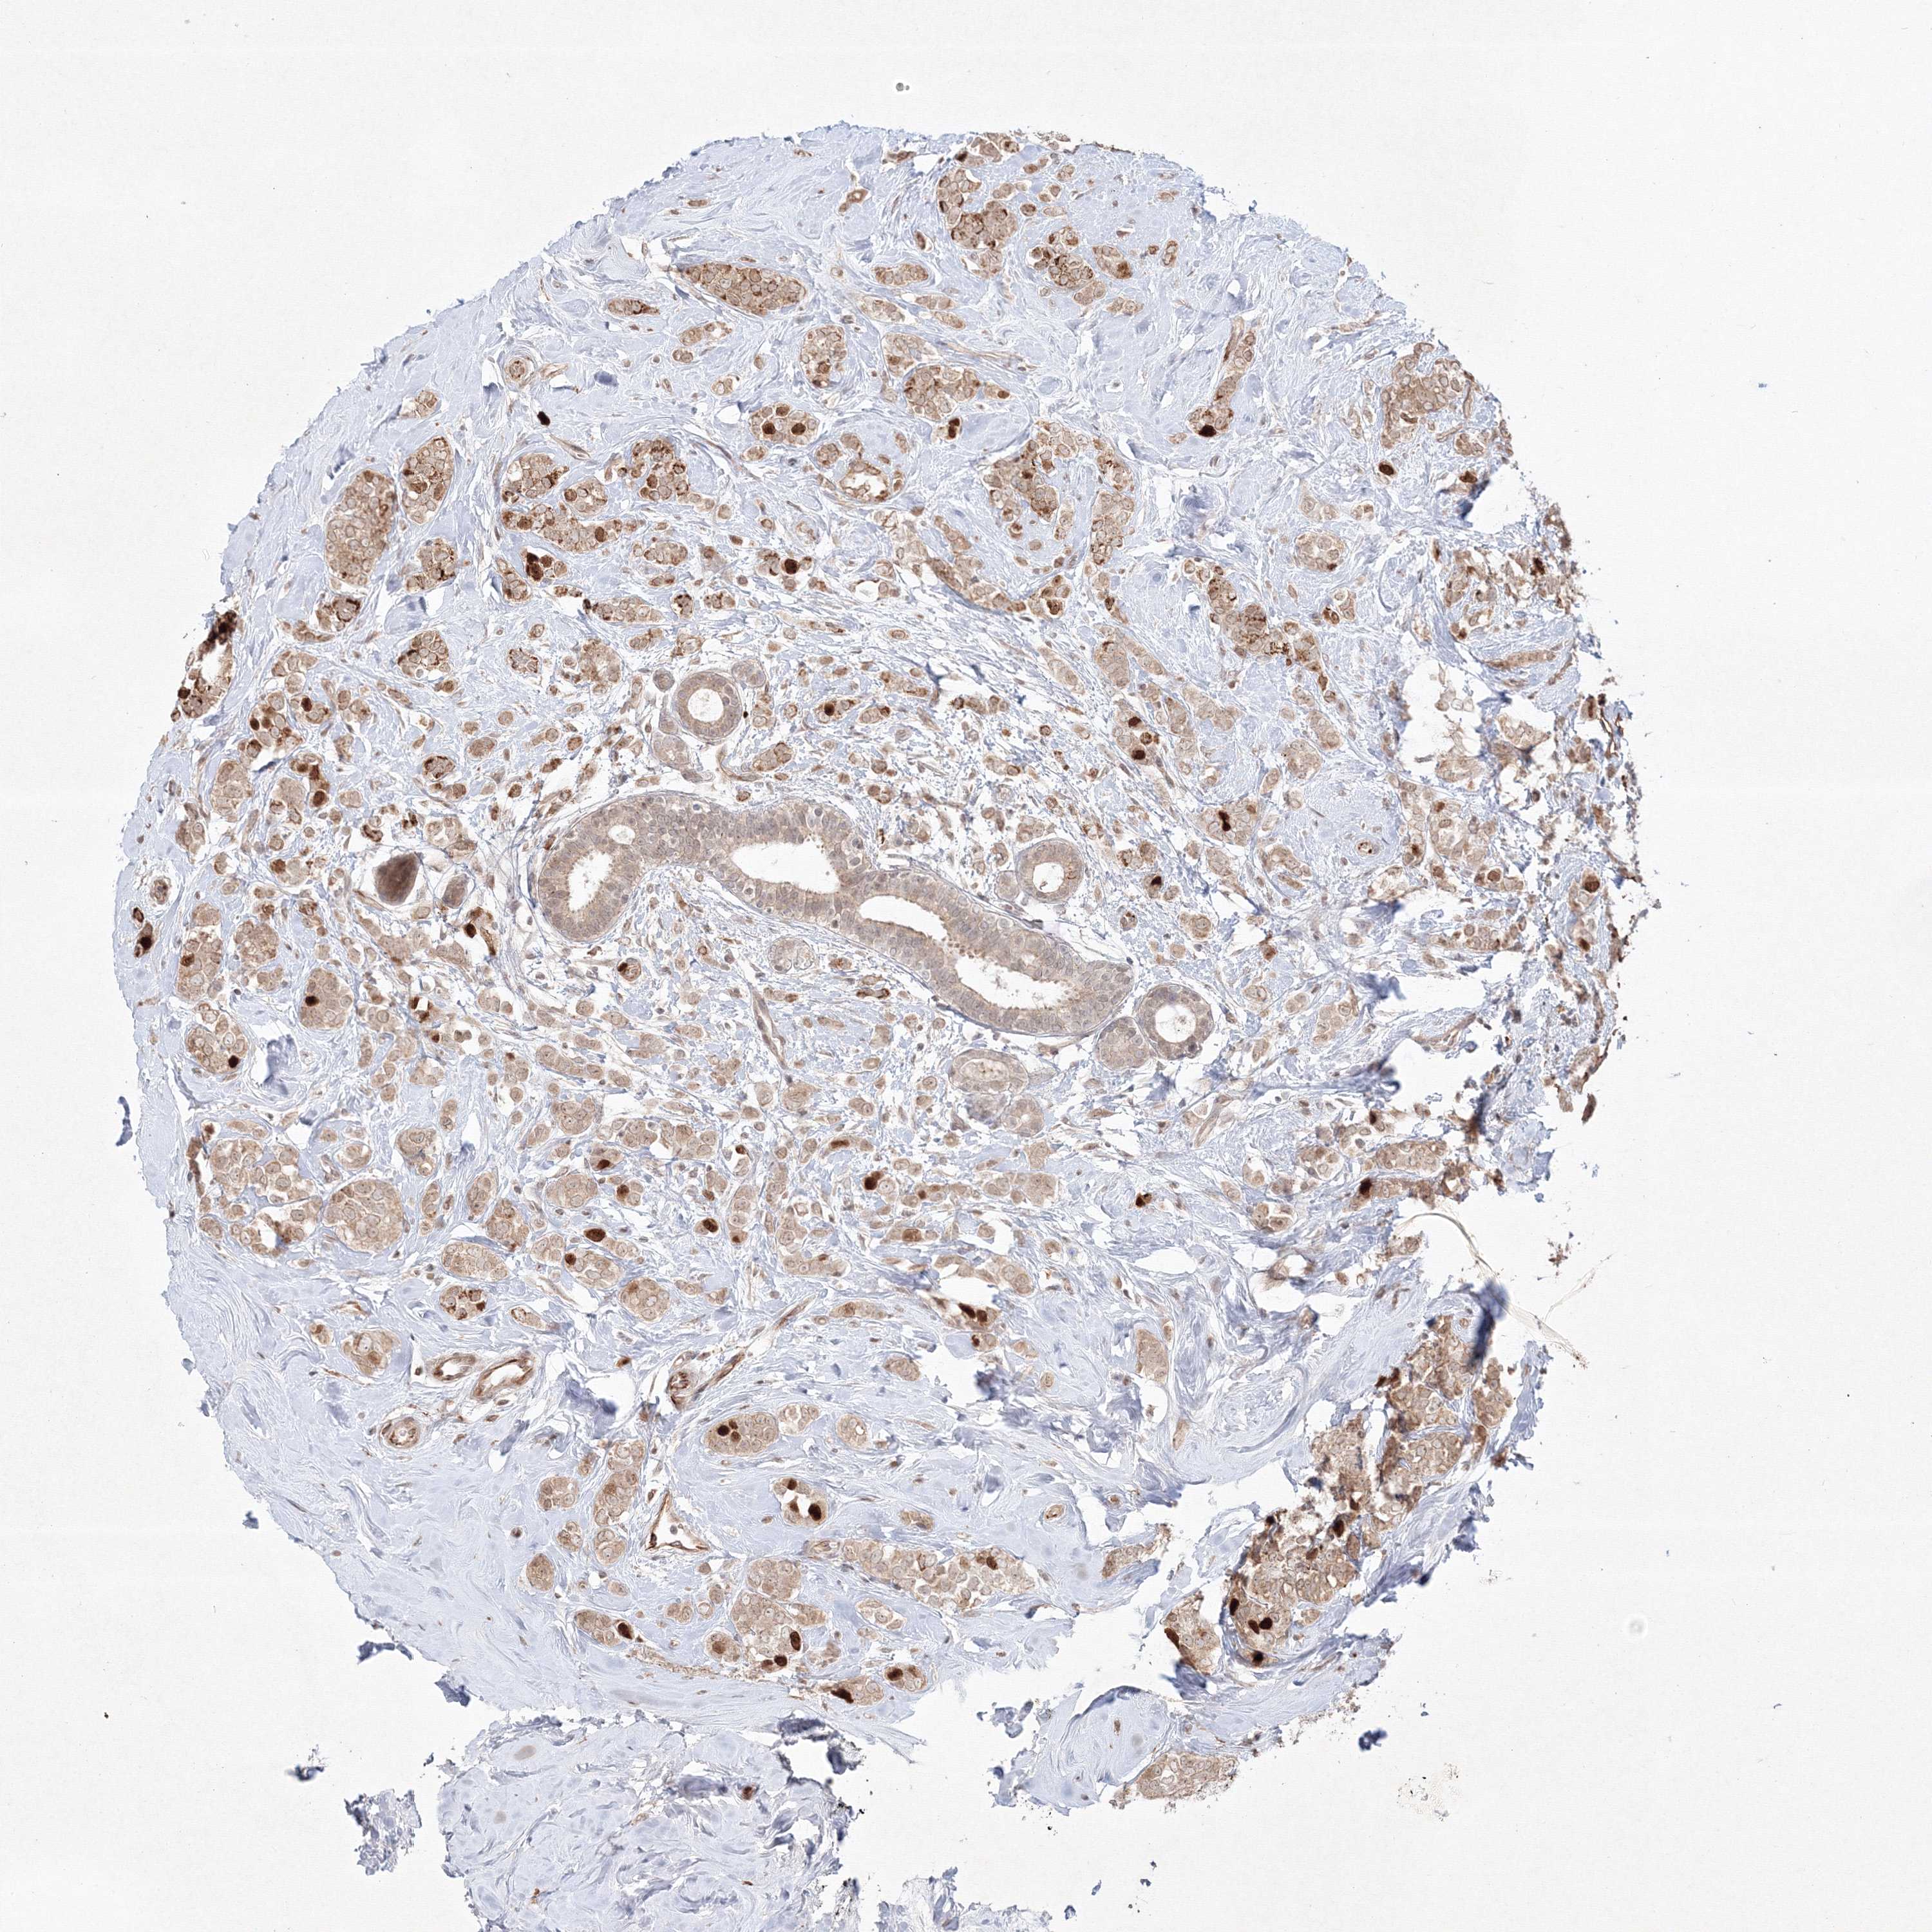

BRCA TCGA BRCA VALIDATION PROTEIN EXPRESSION